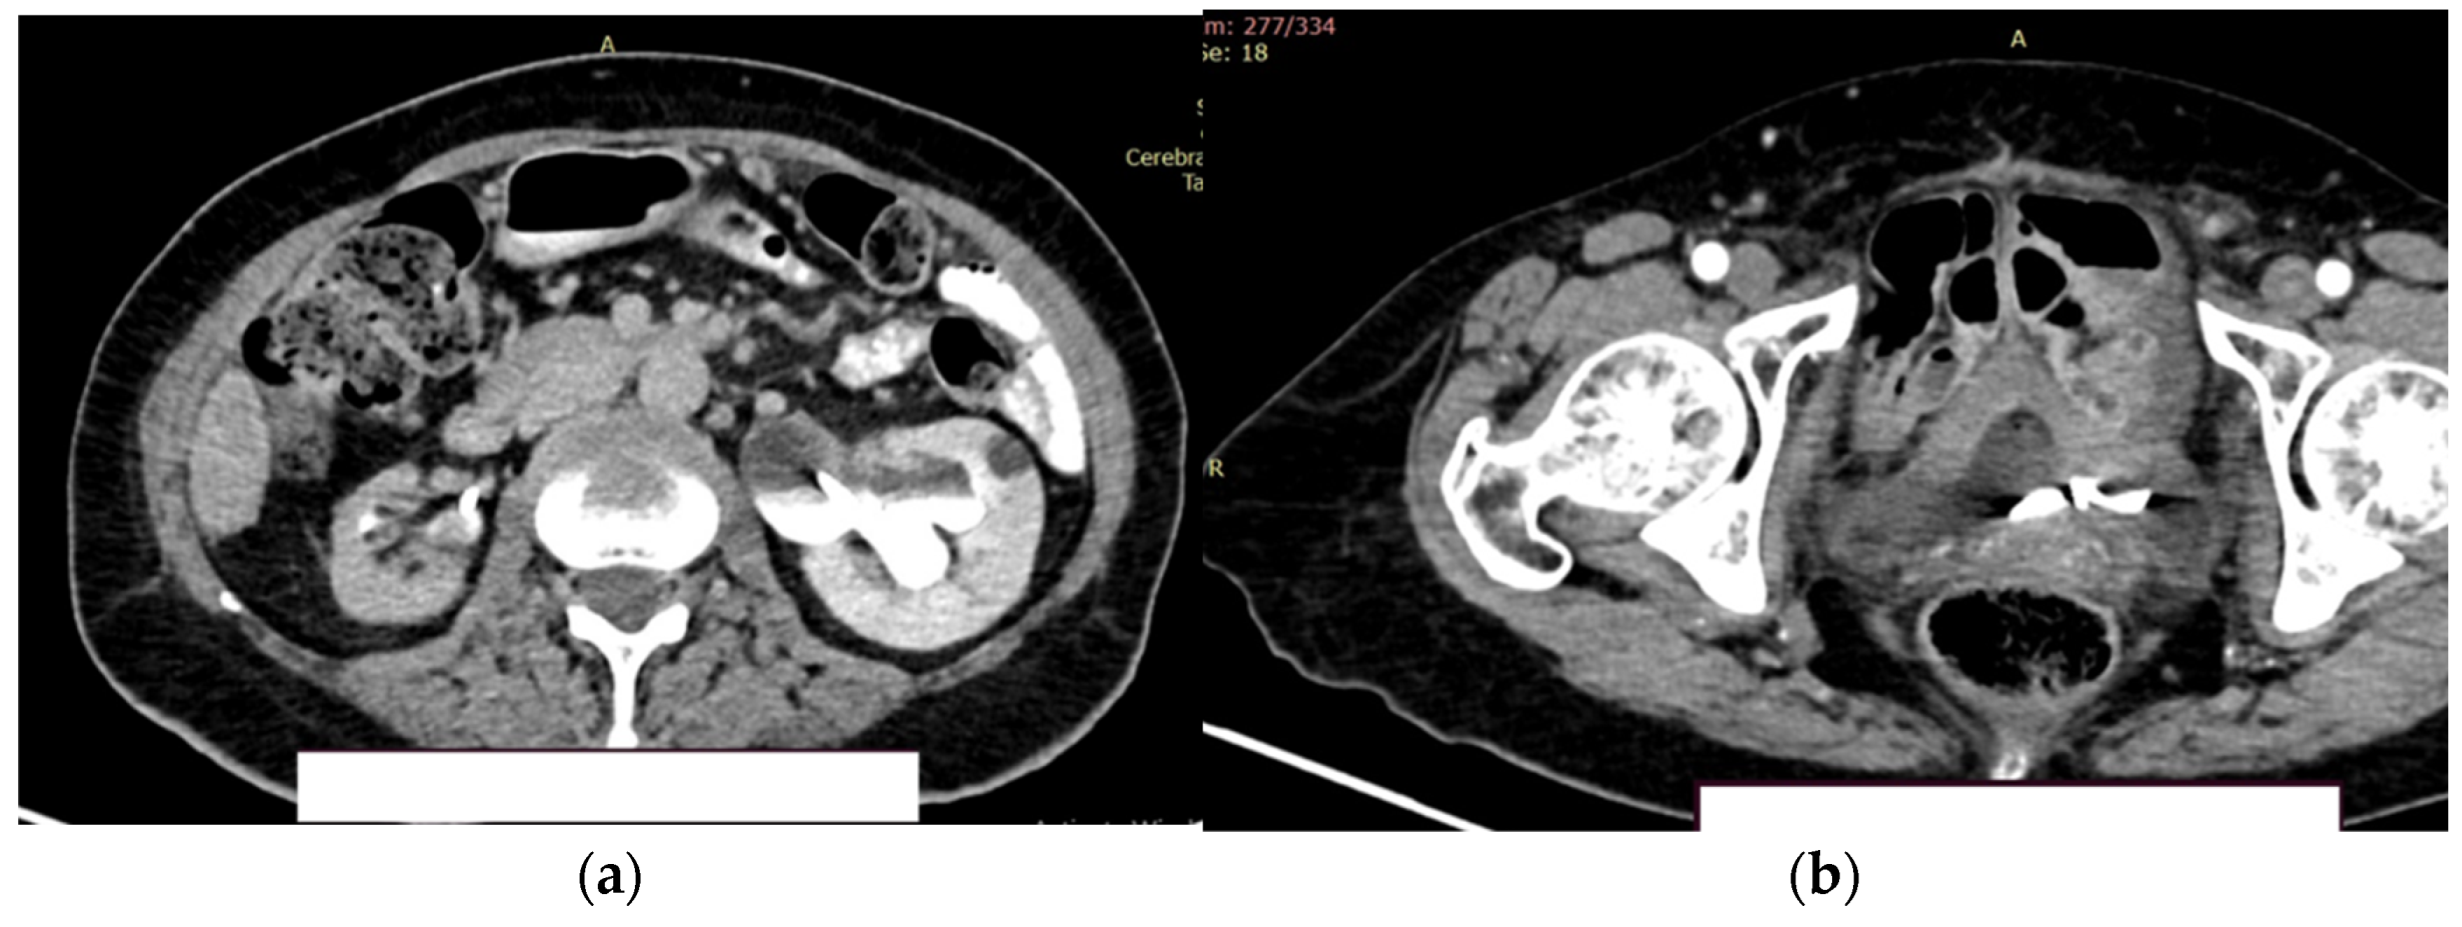

The right kidney is hypotrophic, with the presence of ureteral stent, without stones, without stasis and presence of secretion. Left kidney is with normal position of the stent, II/III grade hydronephrosis, secretion and excretion present. A retroperitoneal lymph node, measuring up to 10 mm, was observed, with some calcification. (Figure 9a).

In the urinary bladder, concentrically thickened walls are described. It cannot be assessed if the distal, intravesical portion of the ureter present tumors formation (Figure 9b).

Figure 9. Contrast CT aspect. (a) The right kidney is hypotrophic, with a ureteral stent in place, no stasis, and secretion present. The left kidney also has a ureteral stent, with grade II/III hydronephrosis, and both secretion and excretion are present; (b) The walls of the urinary bladder are concentrically thickened. It is unclear whether the distal intravesical portion of the ureter has any tumor formation.